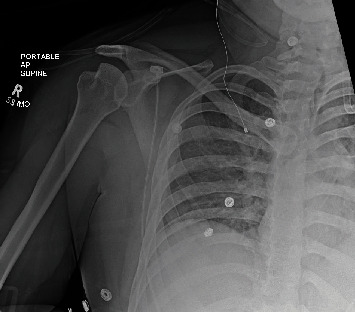

Dislocation of the glenohumeral joint secondary to generalized tonic-clonic seizures is well documented in the medical literature, with posterior dislocation being most commonly described. Still, these occurrences tend to be rare and affect a minority of patients, and fractures associated with dislocations after seizures are even less common. As such, the management of these injuries tends to be quite varied, and there is a paucity of documented cases in the literature. Here, we would like to present two rare cases of anterior shoulder dislocation secondary to seizures, with one patient also sustaining a fracture of the proximal humerus. We would also like to discuss the management and outcomes that have been achieved, since these cases tend to occur in a small number of epileptic patients.